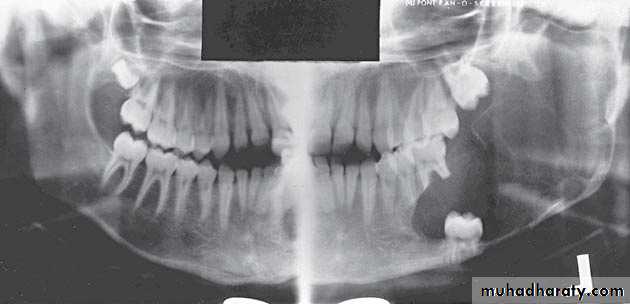

Odontogenic keratocyst:*This cyst develops from the epithelium of the dental lamina instead of the normal tooth which is therefore typically missing from the series.

*The regional teeth are vital.

*Shape: Oval, extending along the body of the mandible with little

mediolateral expansion.

*Minimal displacement of the adjacent teeth , rarely resorbed

Extensive expansion within the cancellous bone.

*Treatment by surgical excision.

A 11-year-old female with swelling on the right side.

impacted canine